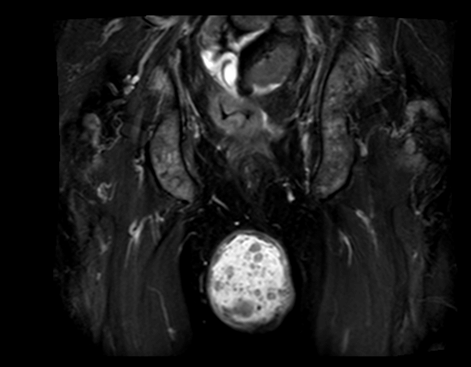

A 55-year-old male diagnosed with prostate cancer in 2010 and underwent radical prostatectomy followed by salvage radiation therapy to the prostatic fossa. He was found to have bone metastasis and since had been treated with hormonal therapy, enzalutamide, abiraterone, radium-223, and taxotere. In April 2016, the patients PSA was >1500 ng/dl. In August 2016, the patient,s was found to have bone marrow involvement with anemia (hemoglobin 6.1 g/dL) and thrombocytopenia (platelets 32x103/ul). In November 2016, the patient began complaining of scrotal pain. Physical examination demonstrated an enlarged scrotum with palpable mass and magnetic resonance imaging (MRI) scan revealed a right testicular hydrocele containing multiple enhancing nodules (Figure 1) (Figure 2) (Figure 3) (Figure 4). At last follow-up on November 10, 2016, the patient continued to have scrotal pain, and required transfusions for anemia and thrombocytopenia and is currently being treated with carboplatin and cabazitaxel.

Cursor on image to zoom/Click text to open image

Figure 3: T2 magnetic resonance imaging scan axial view showing a dominate right testicle with multiple cystic lesions.